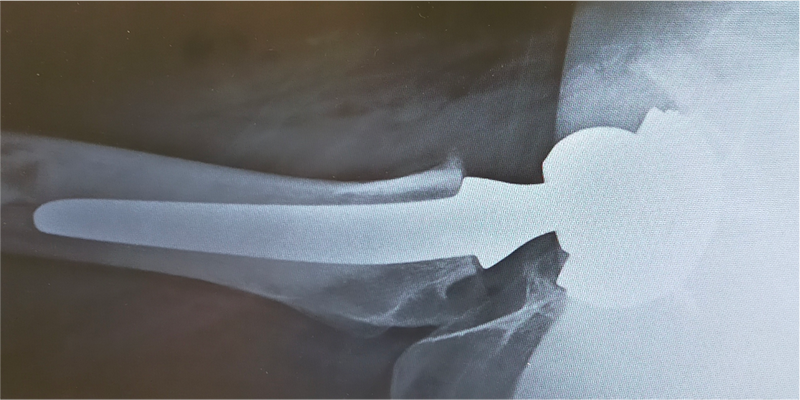

〈手術後のレントゲン〉(側面)

当院にて両側の人工股関節全置換術(THA)を施行。アプローチはAMIS(前方最小侵襲手術)で行い、術中に神経ブロックを併用することで、術後の疼痛コントロールを行い、術翌日から離床、リハビリを進めることができました。術後すぐに歩けることに本人も驚いていました。また、術後は一切の肢位の制限も行っていません。